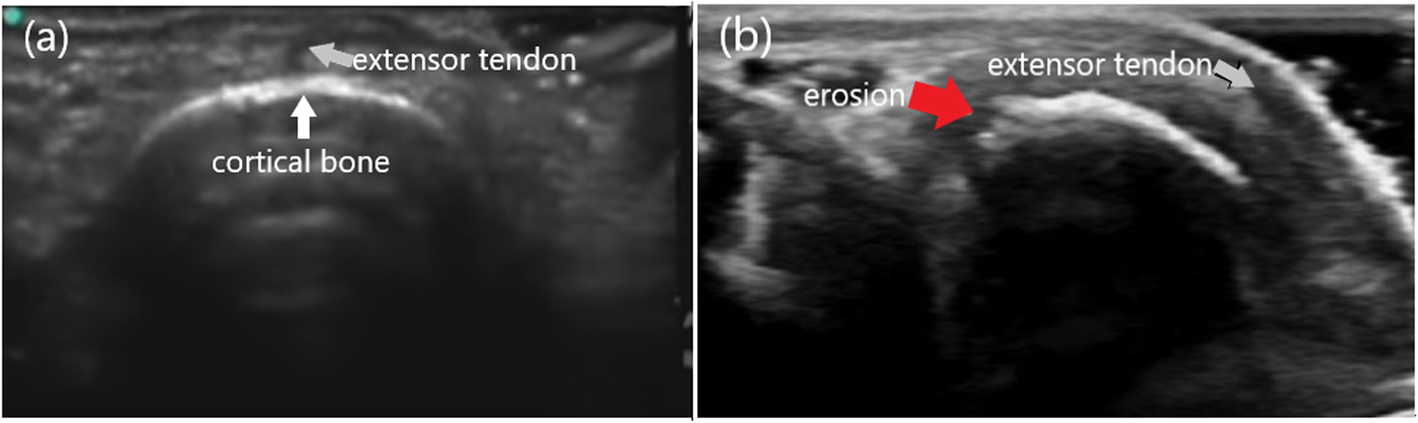

Fig. 3From: A case with Behçet’s disease involving erosive Metacarpophalangeal joint arthritis: the value of ultrasonography in the diagnosis of an ErosionThe transverse images of the second MCP joint in dorsal aspect (a): A normal cortical bone (white arrow) structure of the second MCP joint. (b): The appearance of an erosion (red arrow) in the boneBack to article page